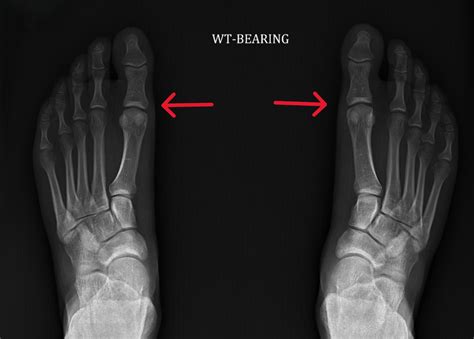

Turf toe is technically known as a metatarsophalangeal (MTP) joint sprain. It occurs when the big toe is forcibly bent upward, often against a rigid surface like artificial turf, damaging the soft tissues that stabilize the joint. This tissue complex, known as the plantar plate, is crucial for pushing off during walking, running, and jumping.

• Presence of Hallux Valgus or Deformity: If the injury has caused the big toe to deviate, affecting long-term gait and biomechanics.

⚠️ Note: Always consult with an orthopedic foot and ankle specialist to get an MRI or stress X-rays, as these imaging tools are essential to determine if the integrity of the joint is truly compromised enough to warrant surgery.